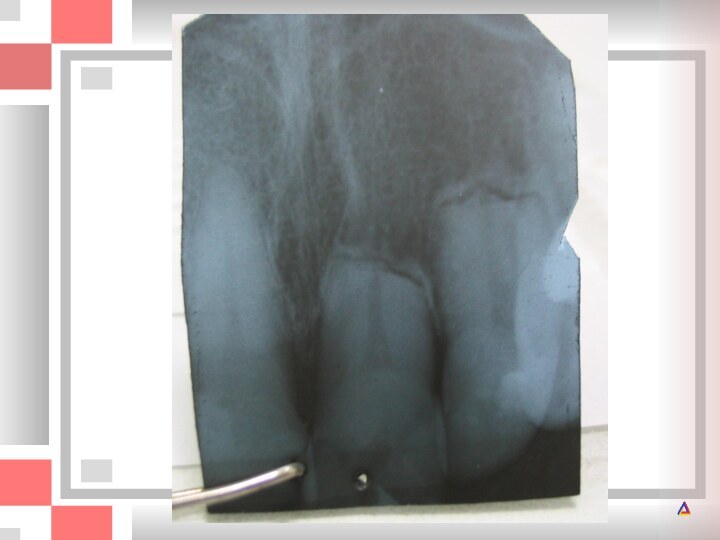

А ‑ верхние молочные центральные резцы приобрели после травмы желтоватый матовый

травмы желтоватый матовый оттенок; Б ‑ на рентгенограмме обнаруживается

практически полная облитерация полостей зубов; В ‑ физиологическая резорбция корней происходит нормально; Г и Д ‑ прорезались постоянные резцы. На губных поверхностях верхних центральных резцов имеются белые матовые участки, свидетельствующие о произошедшей ранее травме.